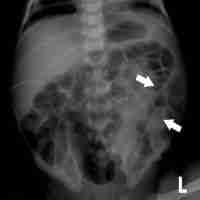

| Abstract | Long-chain 3-hydroxyacyl-CoA dehydrogenase deficiency (LCHADD) is an autosomal recessive condition of impaired beta-oxidation. Traditionally, treatment included restriction of dietary long-chain fatty acids via a low-fat diet and supplementation of medium chain triglycerides. In 2020, triheptanoin received FDA approval as an alternative source of medium chain fatty acids for individuals with long-chain fatty acid oxidation disorders (LC-FAOD). We present a case of a moderately preterm neonate born at 33 2/7 weeks gestational age with LCHADD who received triheptanoin and developed necrotizing enterocolitis (NEC). Prematurity is known as a major risk factor for NEC, with risk increasing with decreasing gestational age. To our knowledge, NEC has not previously been reported in patients with LCHADD or with triheptanoin use. While metabolic formula is part of the standard of care for LC-FAOD in early life, preterm neonates may benefit from more aggressive attempts to use skimmed human milk to minimize exposure to formula during the risk period for NEC during feed advancement. This risk period may be longer in neonates with LC-FAOD compared to otherwise healthy premature neonates. |